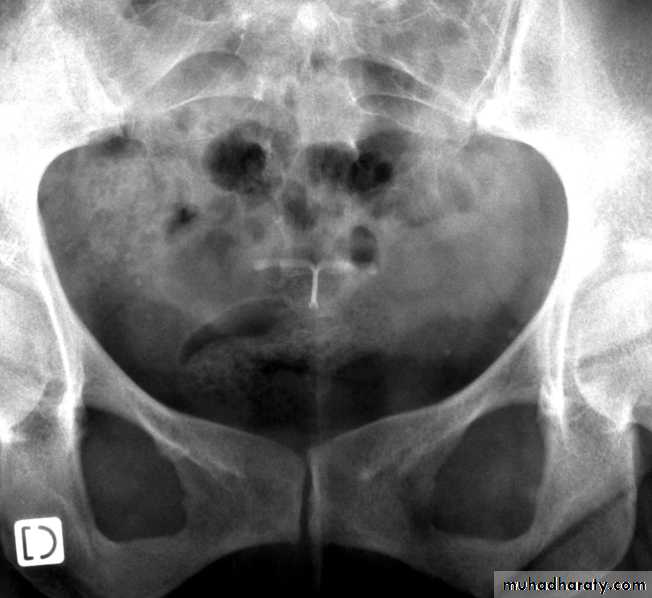

X ray with LNG IUD